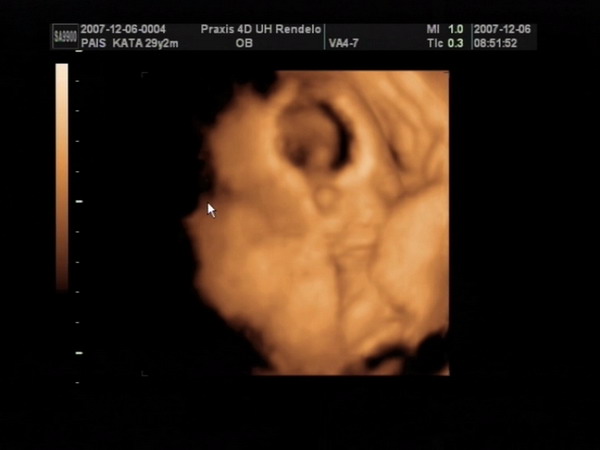

Végre sikerült olyan formátumot csinálni a 4D-s képeinkből, amit ide is fel tudok tenni, úgyhogy büszkén fel is teszem a fotókat :).

Itt pedig a kis pöcsös látható:

Kép

Meli, elméletileg a kiscsaj van alul, és felette a kisfickó - de ez nem 100%, mert dec. 6-án voltunk 4D-n, és azóta lehet, hogy megfordultak. Tegnap voltam dokinál, ő viszont már azt mondta, hogy a végleges helyükön vannak a törpék, már nincsen helyük megfordulni (az viszont nem látszott tegnap, hogy melyik van alul-felül). Mikuláskor kb. 35 dkg-ok voltak, tegnap csak a fejüket mérte a doki bácsi. Minden rendben van velük, de harántfekvéses mindkettő :roll: